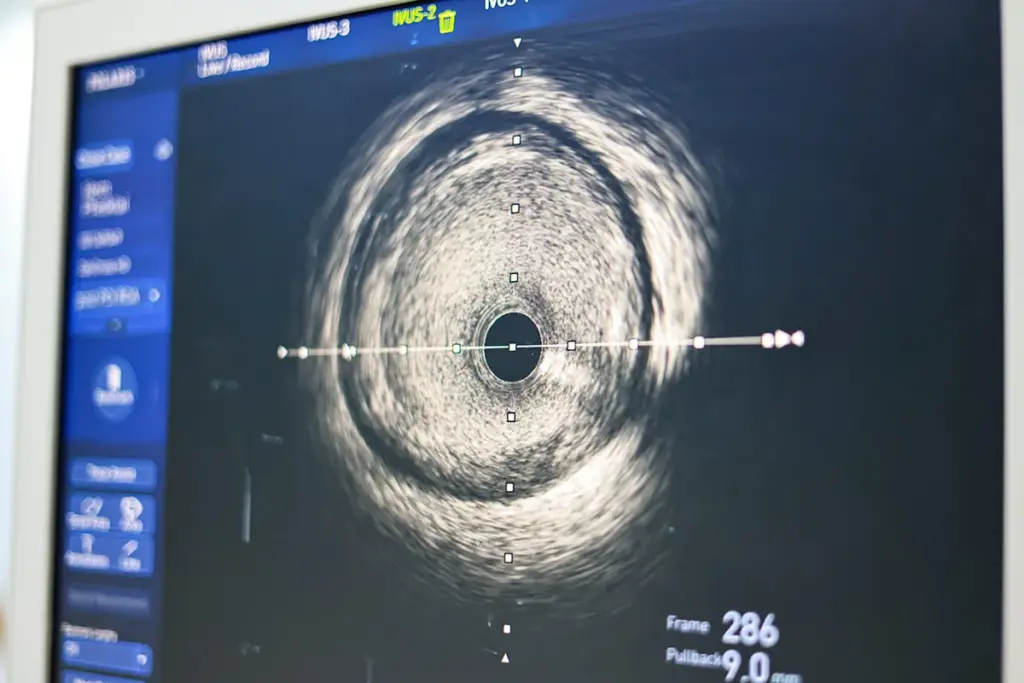

FFR vs. Intravascular Ultrasound (IVUS)

Intravascular Ultrasound (IVUS) gives detailed pictures of the coronary arteries. It shows how much plaque there is and if stents are in the right place. But, FFR tells us if a stenosis affects blood flow.

Using FFR and IVUS together makes diagnosis more accurate. IVUS can spot plaque and tell what it’s made of. FFR then checks if a stenosis is a problem for blood flow.